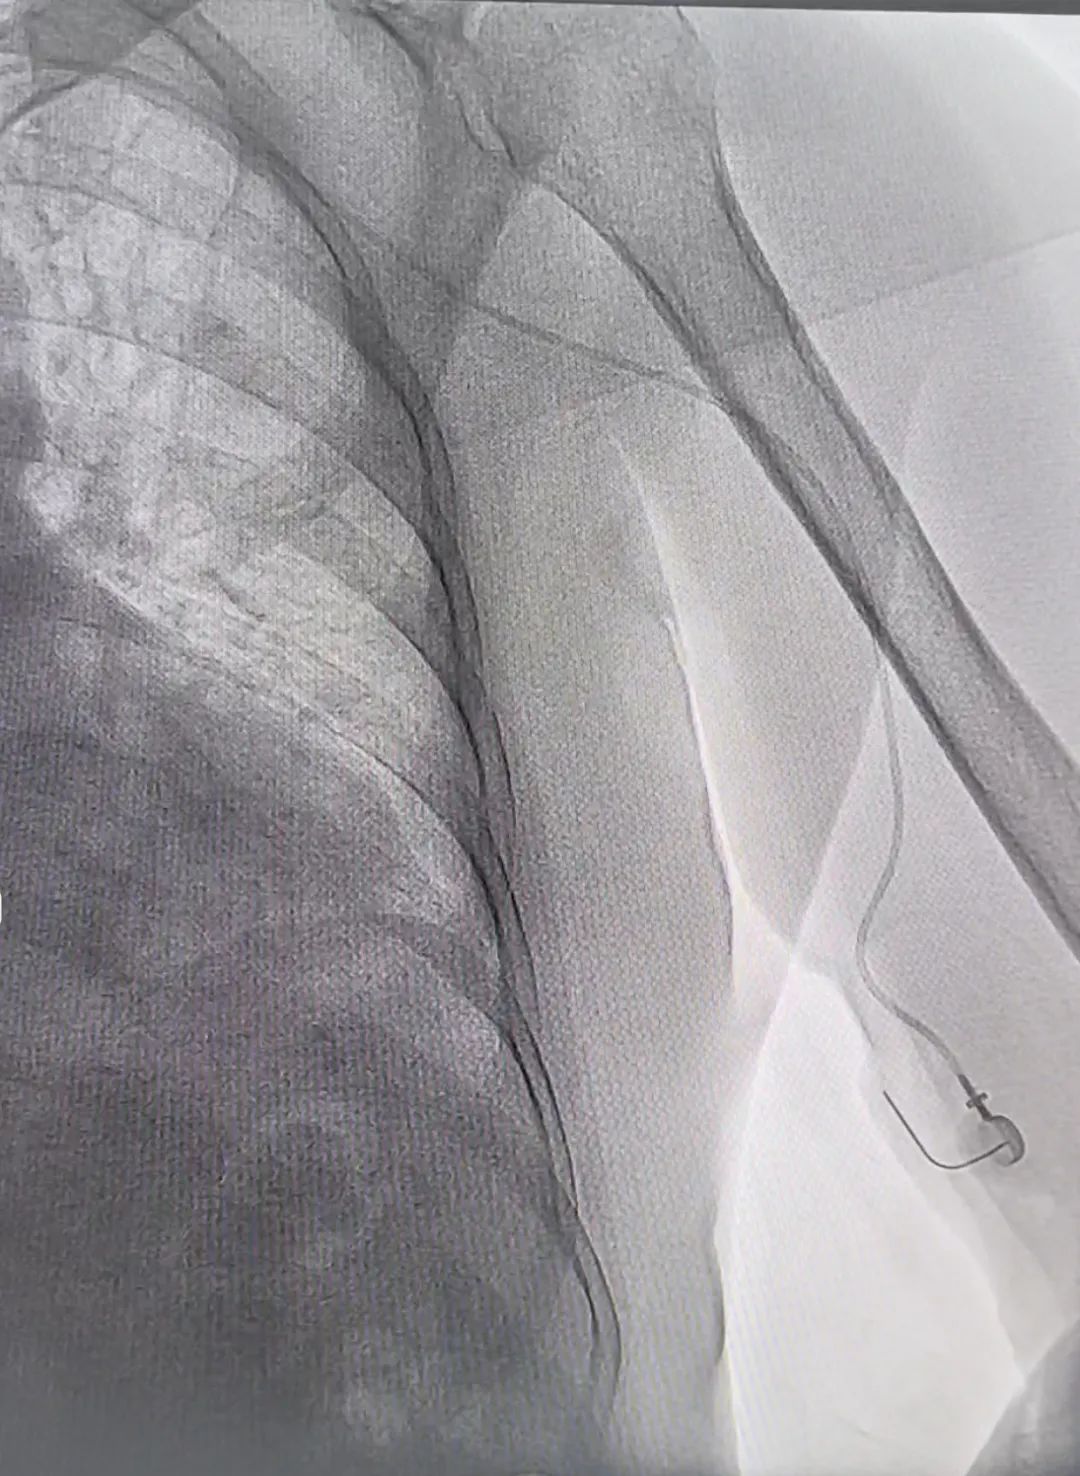

我院乳腺癌患者因多次深静脉置管失败后接受手臂港植入手术。普外一科的医疗团队凭借着精湛的医术和丰富的经验,在超声引导下,精准快速地完成了导管置入。

手术当天,我院普外一科医生拿着“B超神器”在患者体内胳膊上找血管,紧盯监护仪和彩超机。不到20分钟,一个硬币大小的“纽扣”就埋进了皮下,全程只出了一滴血。医生笑着解释:“这‘纽扣’连着心脏的大血管,以后输液直接往这儿扎,再也不用满胳膊找血管了!”